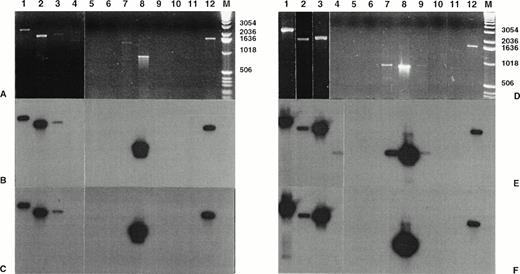

Standard PCR of the RT-PCR assay allowed the detection of NPM-ALK transcripts in 2 of the 15 CD30+ primary CTCL (cases no. 8 and 10) and in 3 of the 11 CD30+ secondary cutaneous lymphoma (cases no. 1, 2, and 3; Fig 2 and data not shown). Furthermore, the nested PCR allowed the detection of the NPM-ALK transcript in 1 of the 11 LyP (case no. 4); in 7 (cases no. 5 through 11) of the 15 CD30+ primary CTCL, including the above-mentioned 2 cases; and in the 3 previously detected cases of the 11 CD30+ secondary cutaneous lymphomas. After ethidium bromide staining showing the same sized amplicons, these results were confirmed both by direct sequencing and by Southern blot hybridization with the junction-specific oligoprobe NPM-ALK-J. The study of MF and BID samples did not show any NPM-ALK transcript after the standard PCR of the RT-PCR assay. However, nested amplification showed NPM-ALK specific amplicons in 6 of the 27 MF and in 1 eczema of the 16 BID samples (data not shown).

Detection of NPM-ALK and reciprocal ALK-NPM transcripts by nested RT-PCR. Total RNA was extracted from frozen skin biopsies or cultured cells and submitted to nested RT-PCR analysis, followed by electrophoresis on 2% agarose gel. Lanes 1, 2 and 3, cases no. 1, 2, and 3, respectively, CD30+ secondary CLCL; lane 4, case no. 4, LyP; lanes 5 through 11, cases no. 5 through 11, CD30+ primary CLCL; lane 12, t(2;5)+SU-DHL-1 cell line; lane 0, no template; lane M, molecular weight marker 100-bp DNA ladder (GIBCO-BRL). Detection of NPM-ALK transcripts: (A) ethidium bromide staining and (B) radioautography. Detection of ALK-NPM transcripts: (C) ethidium bromide staining and (D) radioautography. The gels were transferred to a nylon membrane, hybridized either with the NPM-ALK-J probe (B) or the ALK-NPM-J probe (D), and radioautographed. Sizes are indicated in bases.

Detection of NPM-ALK and reciprocal ALK-NPM transcripts by nested RT-PCR. Total RNA was extracted from frozen skin biopsies or cultured cells and submitted to nested RT-PCR analysis, followed by electrophoresis on 2% agarose gel. Lanes 1, 2 and 3, cases no. 1, 2, and 3, respectively, CD30+ secondary CLCL; lane 4, case no. 4, LyP; lanes 5 through 11, cases no. 5 through 11, CD30+ primary CLCL; lane 12, t(2;5)+SU-DHL-1 cell line; lane 0, no template; lane M, molecular weight marker 100-bp DNA ladder (GIBCO-BRL). Detection of NPM-ALK transcripts: (A) ethidium bromide staining and (B) radioautography. Detection of ALK-NPM transcripts: (C) ethidium bromide staining and (D) radioautography. The gels were transferred to a nylon membrane, hybridized either with the NPM-ALK-J probe (B) or the ALK-NPM-J probe (D), and radioautographed. Sizes are indicated in bases.

The standard RT-PCR assay showed no amplicon after electrophoresis staining (Fig 2 and data not shown). Nested PCR allowed the amplification of the same-sized products (127 bp) visible on gel staining for the same 3 cases positive with the DNA-PCR assay on derivative chromosome 2 (cases no. 2, 3, and 8; 2 CD30+secondary CTCL and 1 CD30+ primary CTCL). The specificity of the results was confirmed by Southern blotting with ALKNPM-J probe and by DNA sequencing of the nested RT-PCR products. No reciprocal transcript was detected in the other cases including MF and BID cases even after nested RT-PCR and Southern blotting.